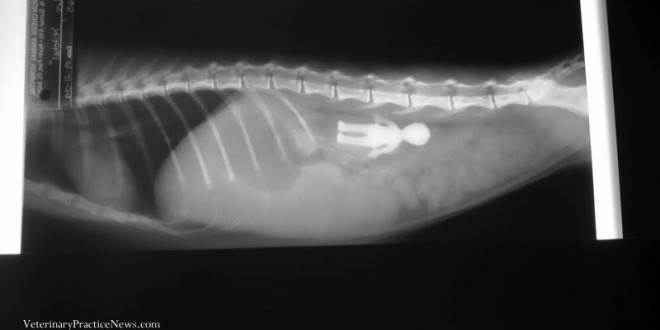

收好你的襪子、黃色小鴨跟燈泡!不然它們會出現在你家毛小孩胃裡!

xraykittenalien(1)